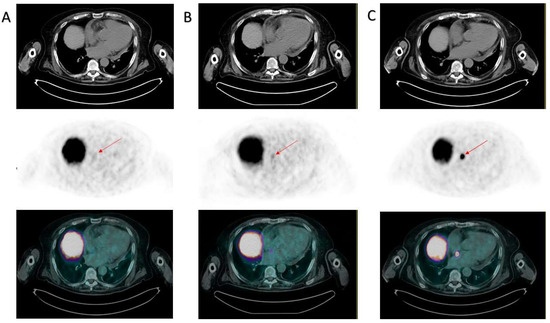

Gandini, A.; Bauckneht, M.; Sofia, L.; Tomasello, L.; Fornarini, G.; Zanardi, E. Cardiac Metastasis from Prostate Cancer: A Case Study Underlying the Crucial Role of the PSMA PET/CT. Diagnostics 2023, 13, 2733. https://doi.org/10.3390/diagnostics13172733